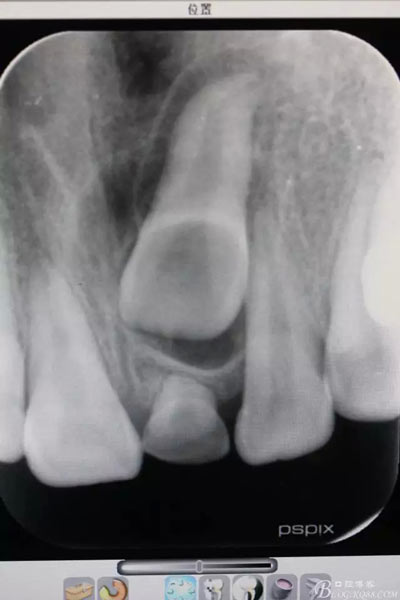

圖1.術(shù)前根尖片影像檢查:21根尖1/3彎曲,牙冠上方有一致密團(tuán)塊影。左乳Ⅰ滯留

圖20.術(shù)后的根尖片影像檢查:21移動(dòng)約 3mm距離,牙冠方向基本正常,半年后復(fù)查,定正畸治療方案